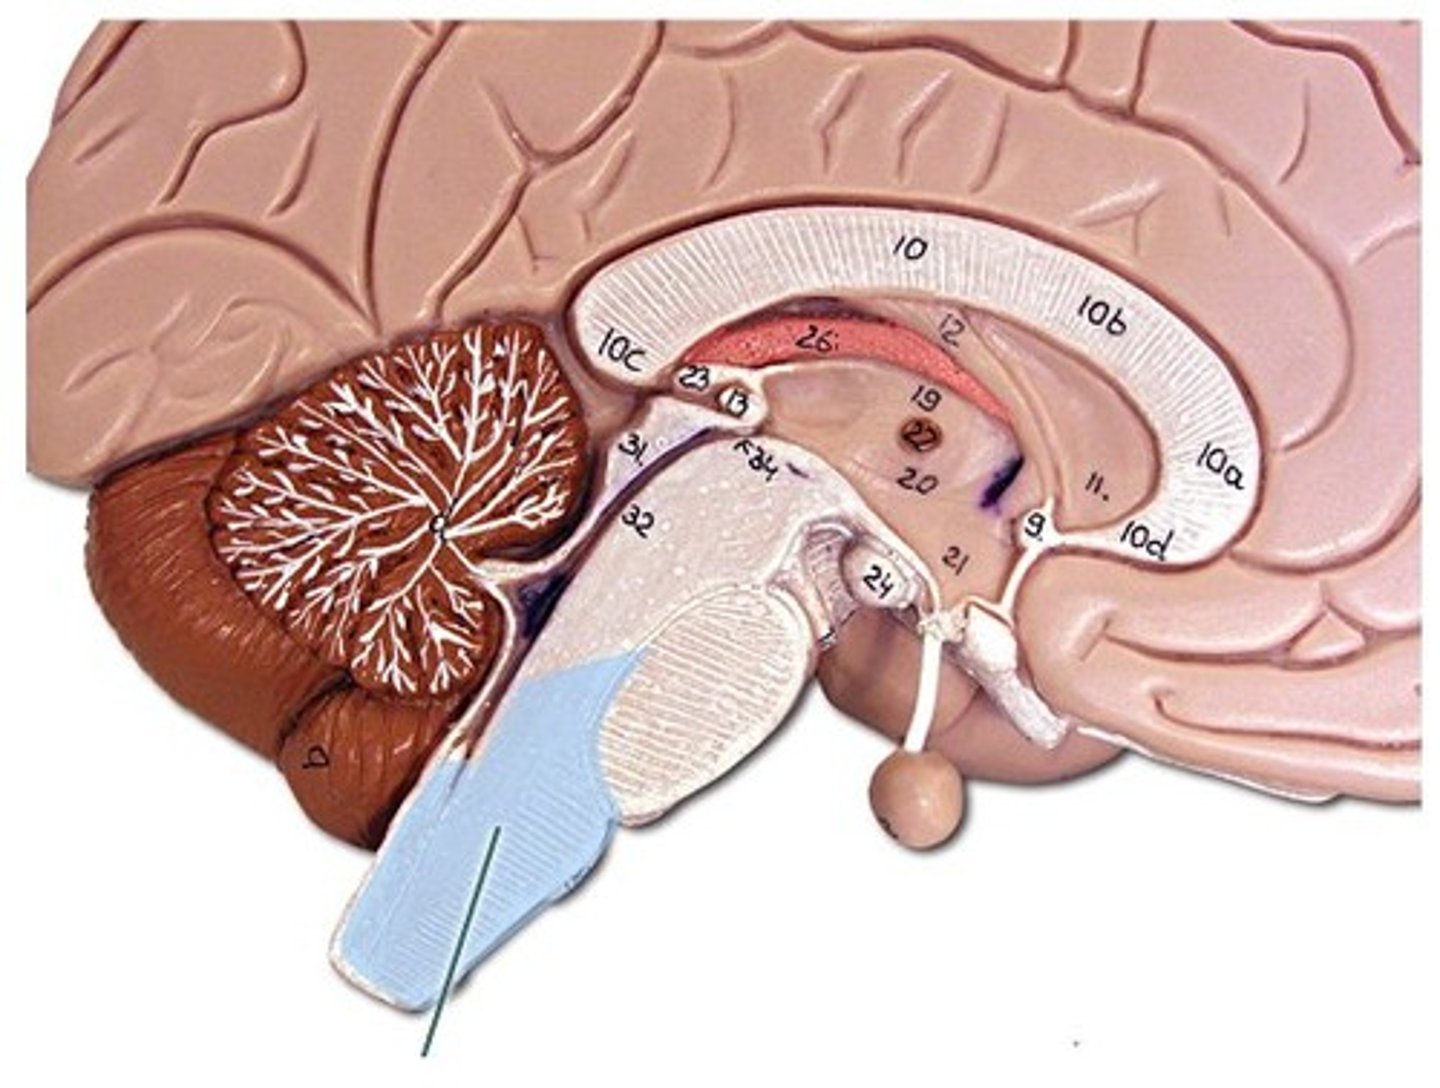

telencephalon

has cerebrum and lateral ventricles

diencephalon

has thalamus, hypothalamus, epithalamus and 3rd ventricle

mesencephalon

or mid brain and its aqueduct

Metencephalon

has pons, cerebrellum, and upper part of the 4th ventricle

Myelencephalon

has medulla oblongata and lower 4th ventricle

brain stem

continuous with the spinal cord and consists of the medulla oblongata, pons, and midbrain

Cerebellum

posterior part of the brain that coordinates muscle movements and maintains balance

Cerebrum (telencephalon)

supported on diencephalon and brain stem

falx celebri

large, sickle-shaped, separates the cerebral hemispheres

tentorium cerebelli

2nd largest, crescent-shaped, separates cerebrum (occipital lobes) from cerebellum (arrow #5)

falx cerebelli

seperates the two hemispheres of the cerebellum. it lies inferior to the tentorium cerebelli, separating cerebellar hemispheres (arrow #7)

diaphragm sellae

smallest infolding covering pituitary gland & sella turcica